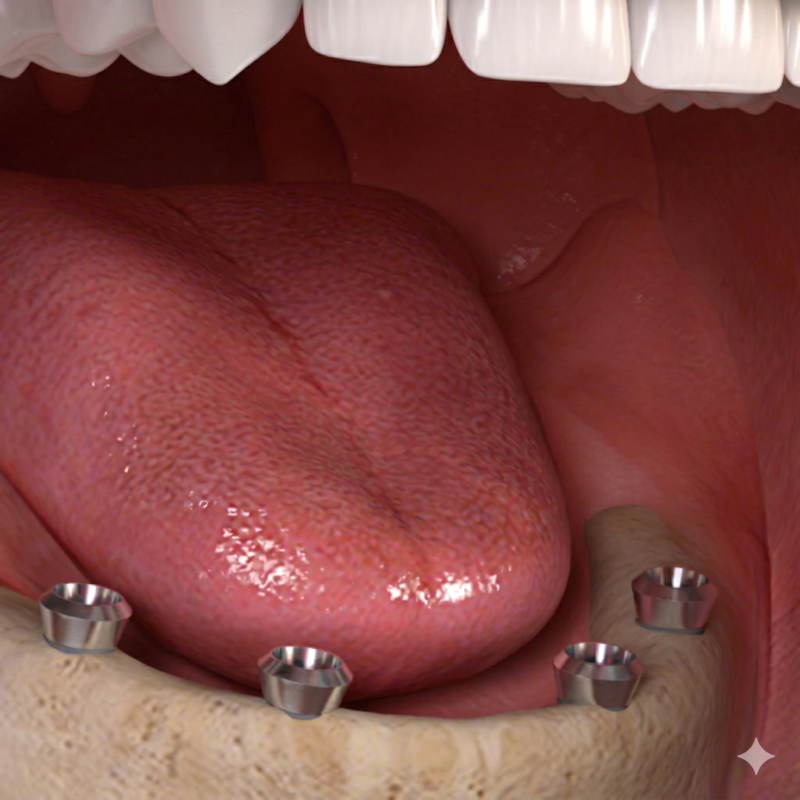

3. ATTACHING THE OVERDENTURES

During your return visit, your dentist takes a panoramic x-ray to check if the implant posts is successfully integrated with the jaw bone. Your dentists takes tooth impressions to construct your permanent dentures in the dental labs. On its delivery, locators, balls or bars are screwed into the implant posts with the dentures snapped over securely over.

4. ADJUSTMENTS AND RE-CHECKS

After receiving your final dentures, your dentist makes additional visits to double-check that the dentures fit properly and comfortably. Implant supported dentures provide better retention and comfort.